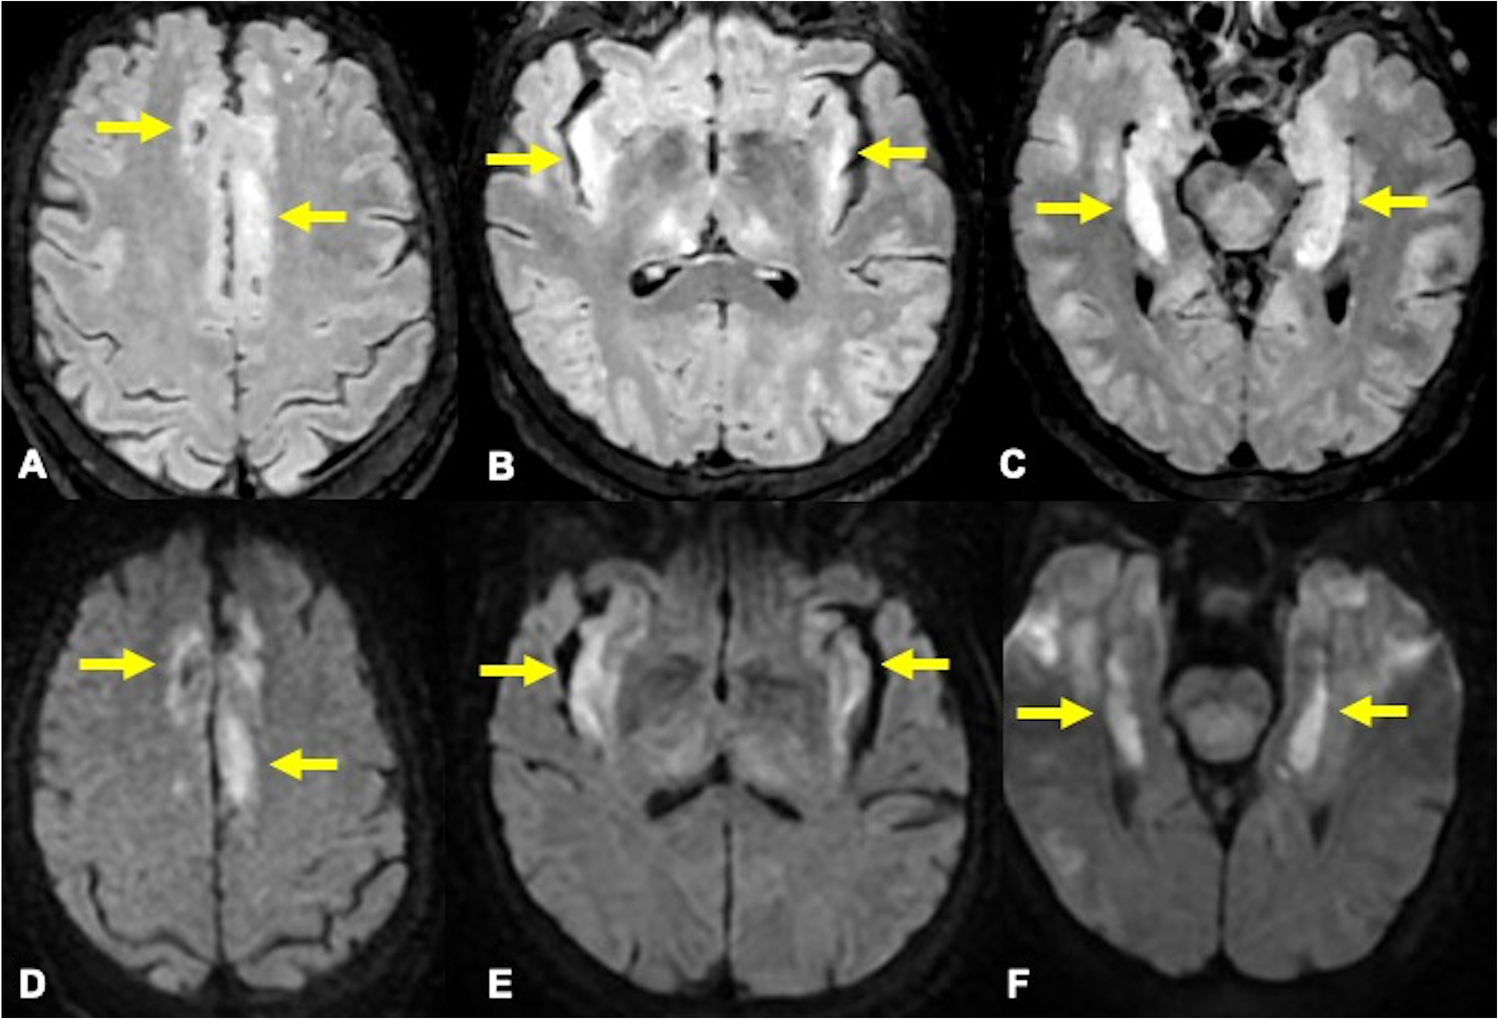

A 70-year-old woman with a prior medical history of cirrhosis and autoimmune hepatitis, presented with altered mental status and seizures. Brain MRI showed bilateral symmetric abnormal high signal on FLAIR and DWI sequences involving the cingulate, insular cortices, bilateral temporal lobes, and thalami (Fig. 1). Plasma ammonium levels were:178 µg/dL. The imaging findings in the clinical context were consistent with hyperammonemic encephalopathy.

Axial FLAIR (A-C) and DWI (D-F) weighted images show abnormal bilateral symmetric high signal in the insular, cingulate cortices and mesial temporal lobes (arrows)